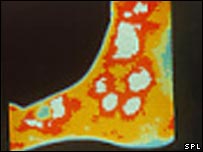

روبہ صحت السر کا حرارتی عکس

دورانِ خون میں خرابی السر کے مندمل ہونے میں رکاوٹ بنتی ہے۔